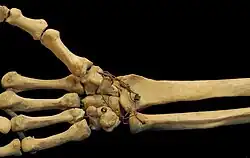

The carpometacarpal (CMC) joints are five joints in the wrist that articulate the distal row of carpal bones and the proximal bases of the five metacarpal bones.

The CMC joint of the thumb or the first CMC joint, also known as the trapeziometacarpal (TMC) joint, differs significantly from the other four CMC joints and is therefore described separately.

Fingers

- The second metacarpal articulates primarily with the trapezoid and secondarily with the trapezium and capitate.

- The third metacarpal articulates primarily with the capitate,

- The fourth metacarpal articulates with the capitate and hamate.

- The fifth metacarpal articulates with the hamate.

Ligaments

These four CMC joints are supported by strong transverse and weaker longitudinal ligaments: the dorsal carpometacarpal ligaments and the volar or palmar carpometacarpal ligaments.[7]

The interosseous ligaments consist of short, thick fibers, and are limited to one part of the carpometacarpal articulation; they connect the contiguous inferior angles of the capitate and hamate with the adjacent surfaces of the third and fourth metacarpal bones.